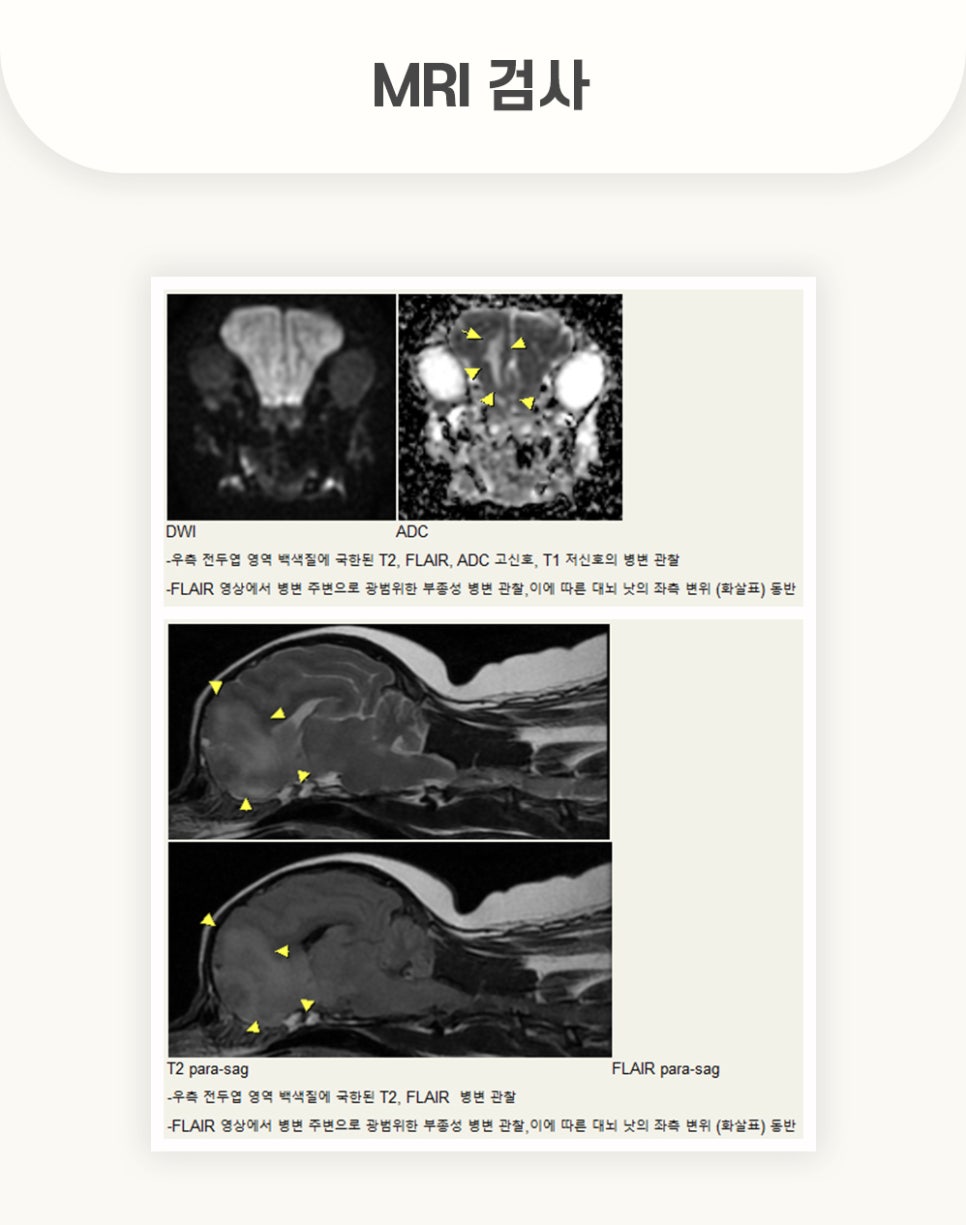

우선적으로 실행한 MRI 촬영 결과, 검사 화면에서 강아지 뇌 종양을 확인할 수 있었습니다.

전두엽 측 뇌수막종과, 원인 불명의 뇌수막염, 후두골 이형성 등이 관찰되었습니다.